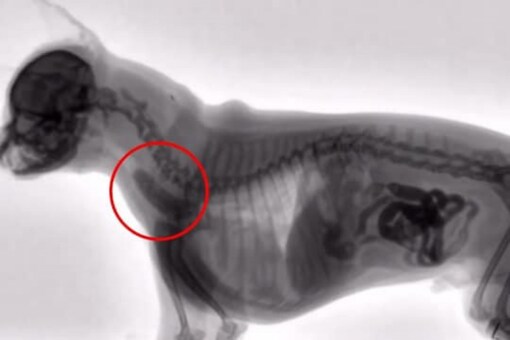

You will usually need X-rays if your cat swallows a sewing needle or other foreign object. Animal CT Pet CT System VET CT Veterinary X-ray Machine. If the injury is not something the vet can assess with just an examination which is usually the case then x-rays will need to be.

Most pet owners dont know how much a cat x-ray costs because they never imagine their feline friends going through one. You will usually need X-rays if your cat swallows a sewing needle or other foreign object. Emergency clinics may charge up to 400.

Show up on X-Ray as white.

0 1000000. Including intravenous fluids and pain relief medication. Vomiting diarrhea and seizures might also cause your vet to call for an X-ray.